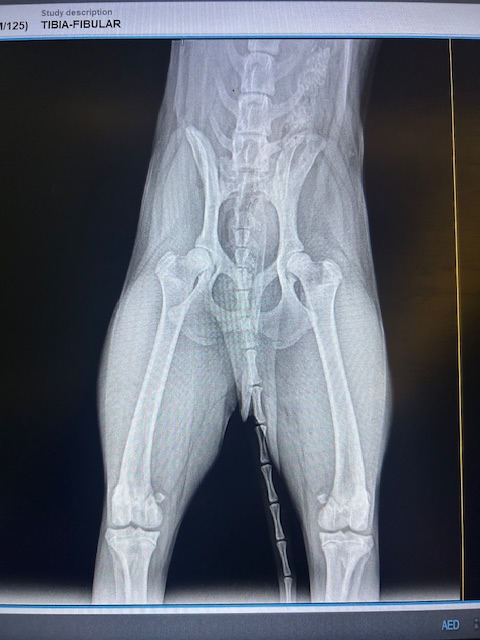

Wir wissen das die Chance jemanden für Lenny zu finden sehr gering sind, aber er ist so ein unglaublich liebenswerter und lebensfroher Hund, sodass wir ihm einfach diese Chance geben müssen... Als wir Lenny fanden, lag er hilflos am Straßenrand – kaum bewegungsfähig, schwer verletzt und allein. Alles deutete darauf hin, dass jemand mit einem Knüppel auf den kleinen Welpen eingeschlagen hatte. Er konnte sich nicht mehr bewegen, sein Blick voller Schmerz – und doch voller Hoffnung, als wir ihn aufnahmen. In der Klinik brachte das Röntgenbild die traurige Wahrheit ans Licht: Zwei Wirbel in seinem Rücken sind verschoben, vermutlich durch den Schlag. Die Folge – eingeklemmte Nerven, die seine Hinterbeine lähmen. Er kann sie nicht gezielt bewegen, streckt sie unkontrolliert von sich. Doch im Wasser sehen wir: Irgendetwas in ihm kämpft weiter, denn beim Schwimmen macht er Bewegungen – wenn auch steif.